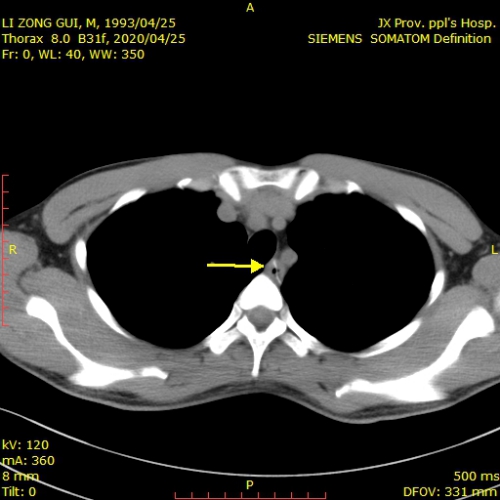

该患者李某某,男,27岁,因误食鸭骨头后胸痛1天入院,患者辗转2家省级三甲医院,完善胸部增强ct均提示异物已贯穿食道,距离主动脉仅2毫米(见下图),建议其手术治疗。

患者胸部ct